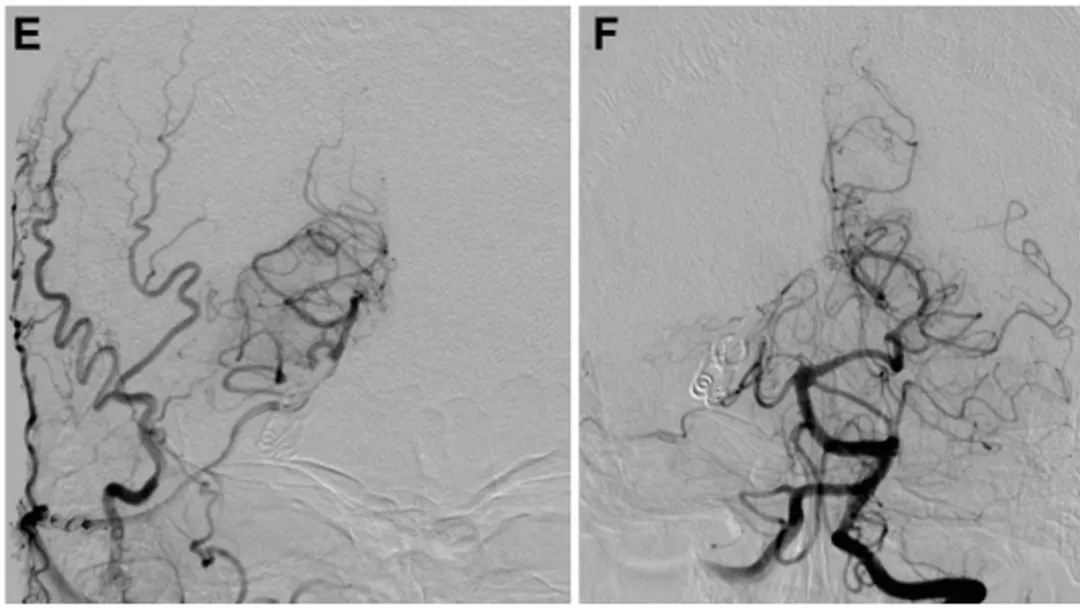

术中通过吲哚菁绿荧光血管造影反复确认,搭桥血管、P3段及PTA血管保持全程通畅,血液供应正常;随后打开动脉瘤,确认瘤体实现完全闭塞,同时完成血栓切除术,清理瘤体内陈旧血栓。整场手术全程保持精准操作,完美避开颅内关键功能区,未损伤任何神经功能。

手术结束后,尹先生的恢复速度远超预期,出院时未出现任何神经功能缺损,无肢体无力、言语障碍、视力模糊等后遗症,日常生活完全能够自理。术后一年随访复查结果显示,颅内搭桥血管依旧保持通畅状态,动脉瘤被彻底孤立,无复发迹象,颅内压迫症状也获得完全缓解。